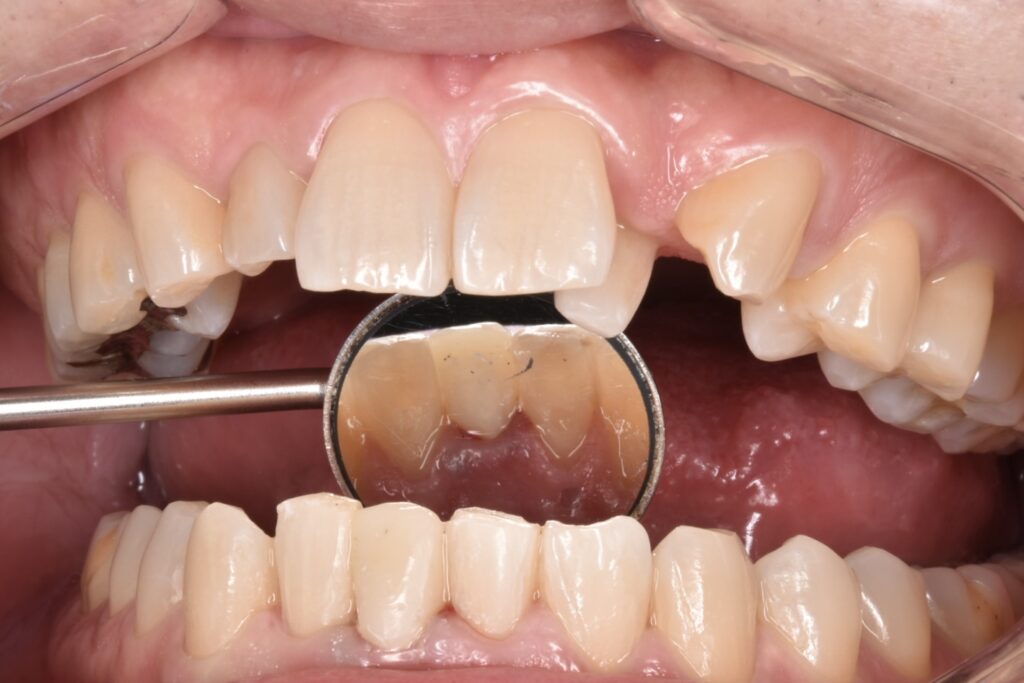

50代男性 下の前歯が東京の歯科で一年ほど前に作られた差し歯で、今回はそれが取れてしまったとご相談いただきました。検査の結果、歯が土台ごと折れていました。折れている場所が歯茎の中の方で折れていて、歯槽骨ギリギリの場所です。

こちらが初診時のレントゲン写真です。歯が水平的に破折していて歯の一部が骨のトップに差し掛かっていることがわかります。

写真の青字:骨のライン

写真ピンク字:歯の断端